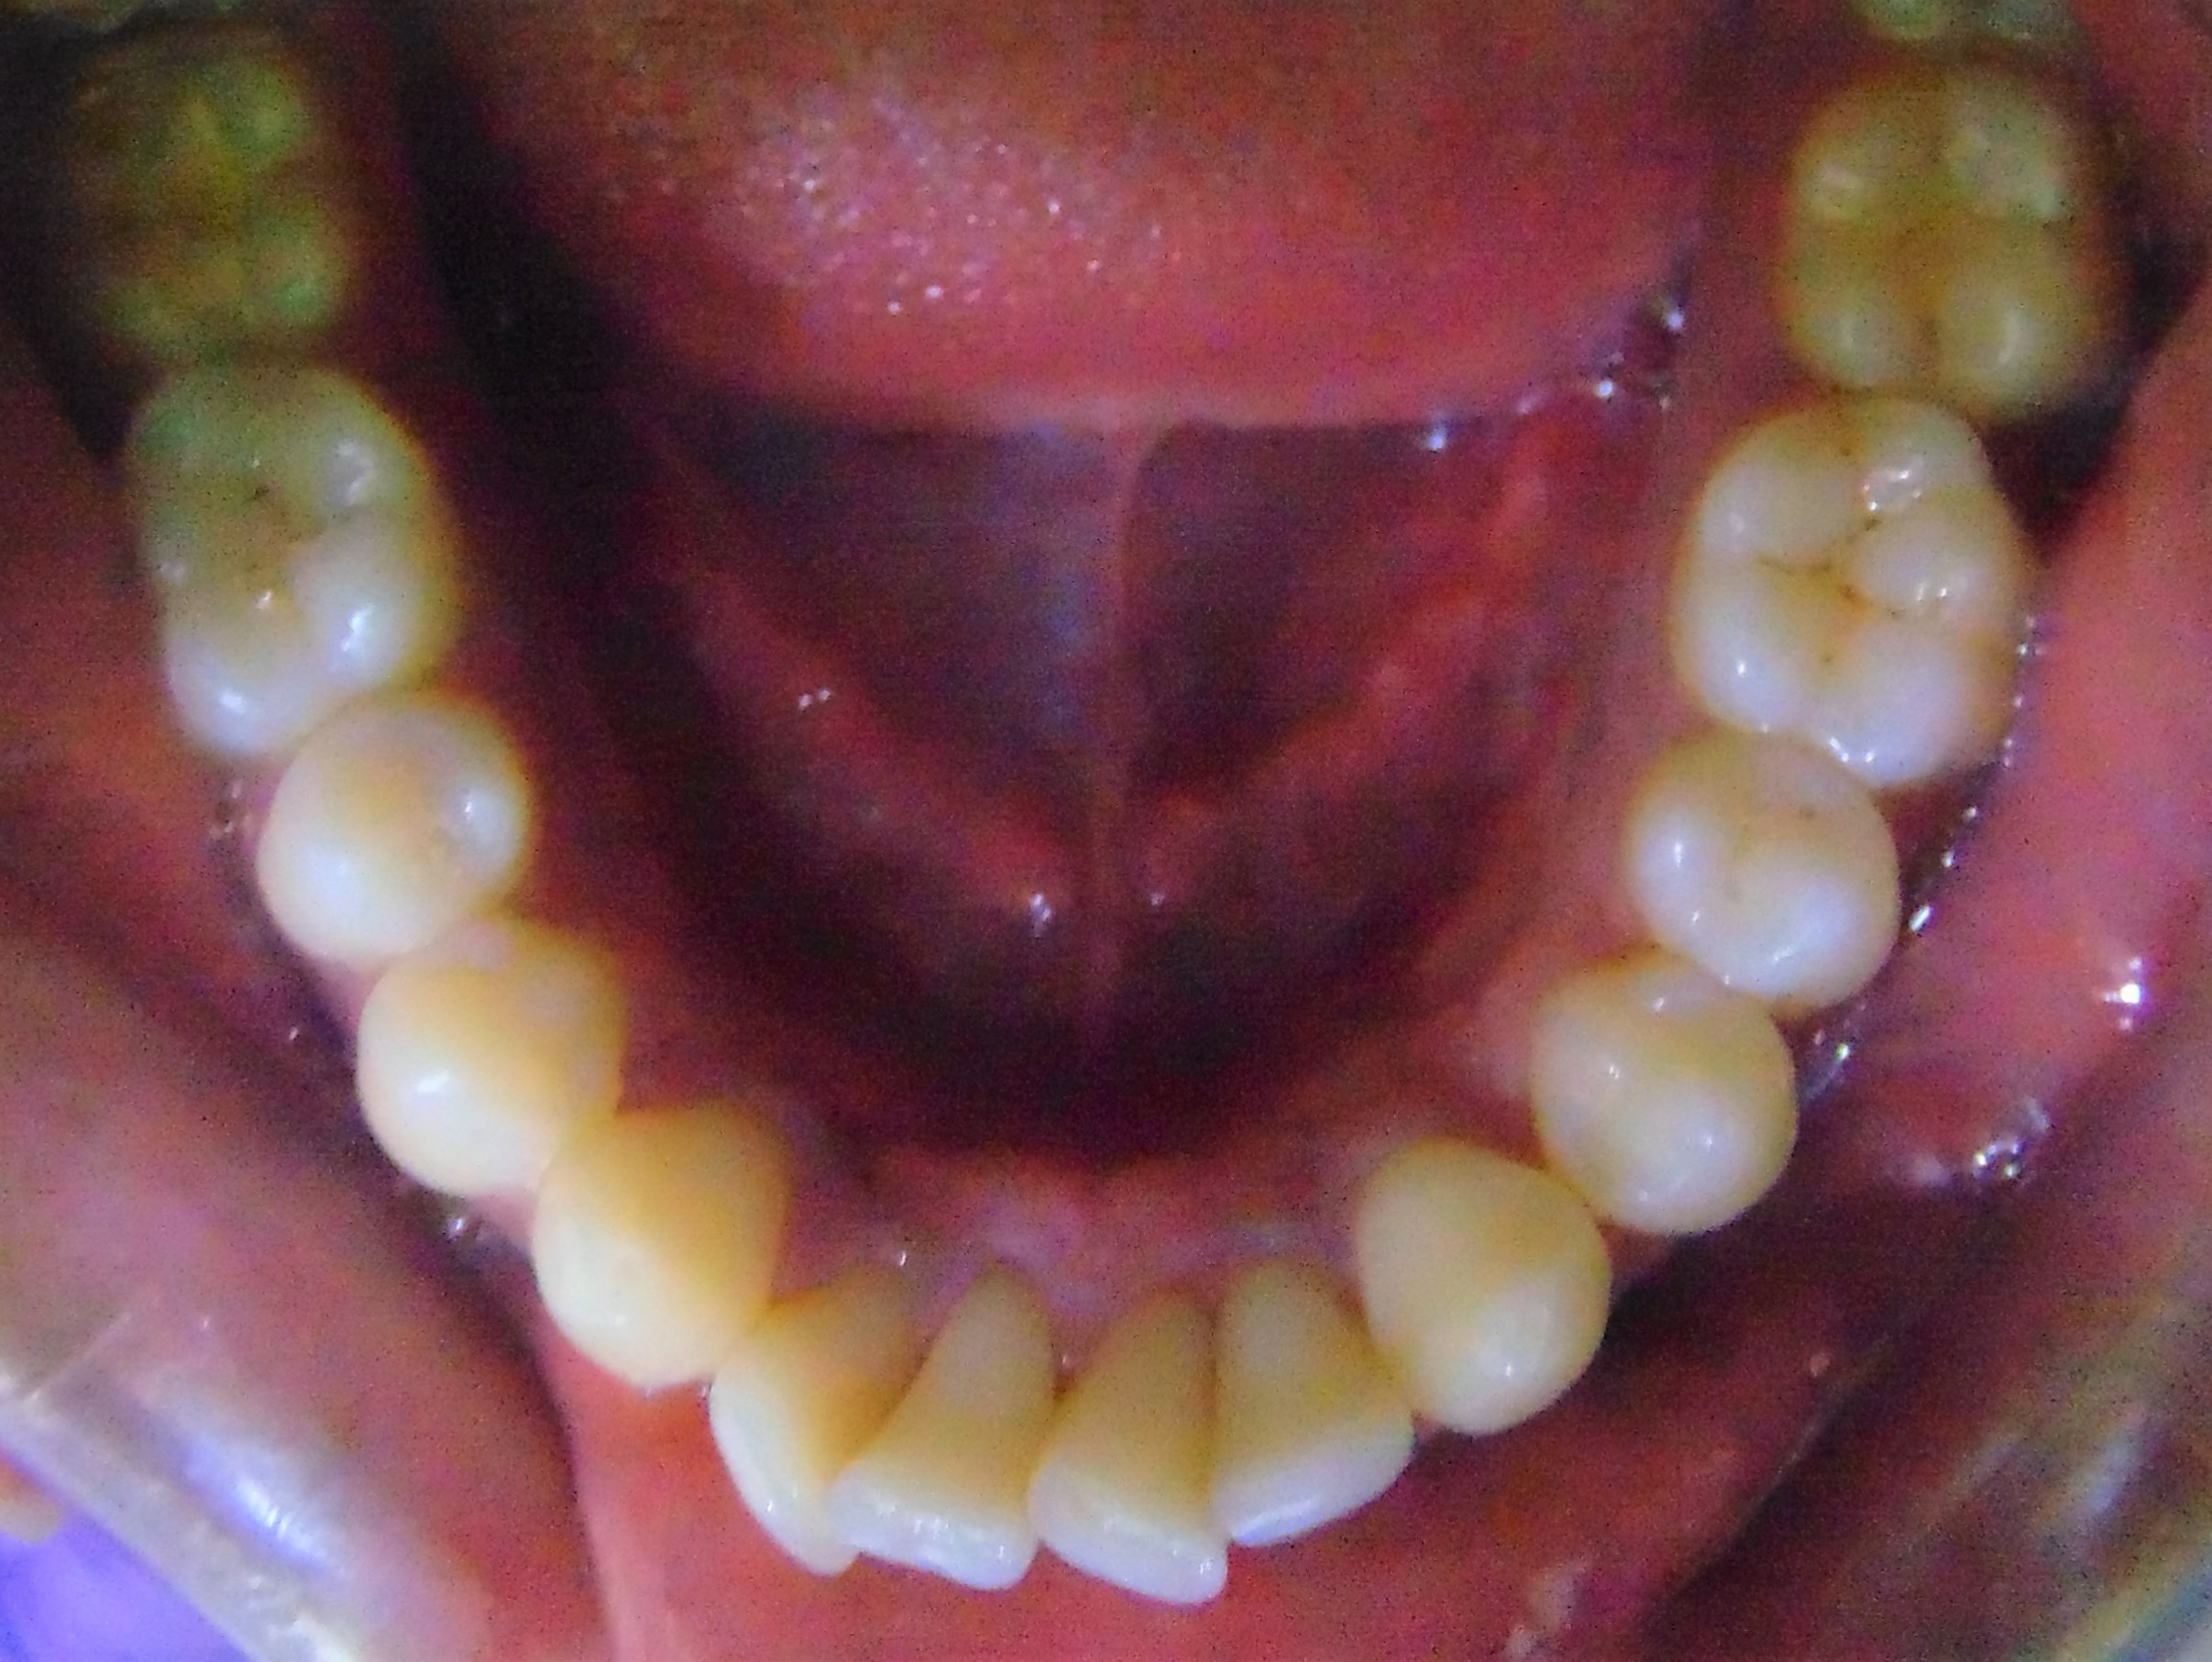

Before

Image 1